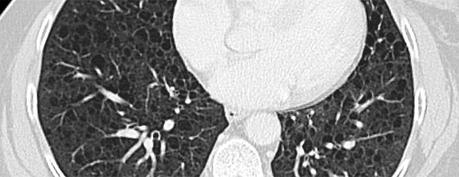

En la TAC se observan imágenes de quistes de paredes delgadas con infiltrados reticulonodulares.